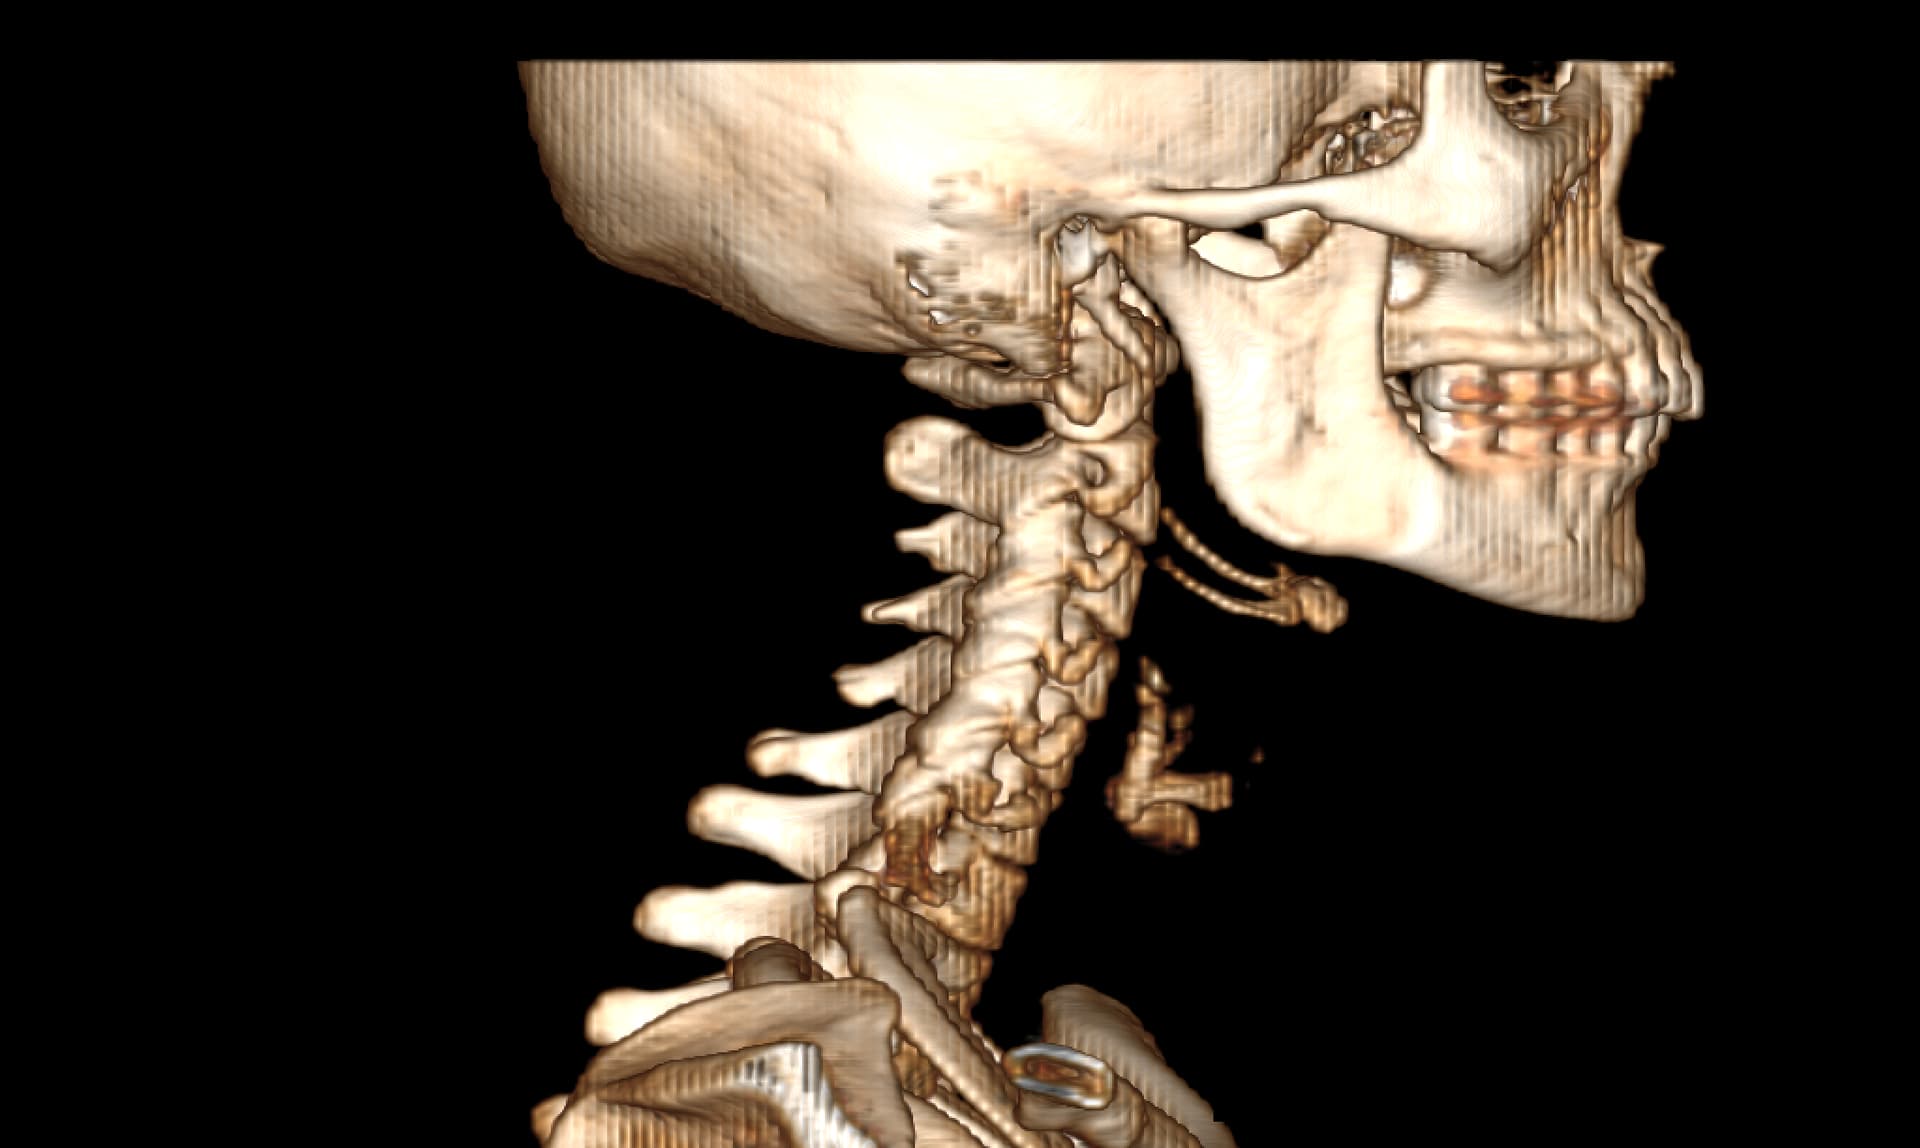

I did have an MRA done at Mayo that showed severe blood flow compression on my left side with my arms up. Because of this test, I went back to UCLA and did tests for Thoracic Outlet Syndrome. The limited tests they can do for this seemed to help. So, I had a left rib resection 2 yrs ago. Before this surgery, I did do a CT w/wo contract to look for Eagles and the report came back saying my stylohyoid was normal. So I went ahead with the thoracic outlet surgery. That surgery got rid of the daily headache I was dealing with. It seemed to have relieved pressure headaches and some of the loss of feeling in my arm. It never helped with the facial pains and dizziness though that I live with. Months after this surgery, I also developed Frozen Shoulder. I found it odd I got this so long after the surgery and when I was in PT. It seemed like the more we tried to use my arm and mess with my neck, the worse it got. I then went back to Mayo and had a head and face MRI that showed compression of my vagus nerve with an artery around my brainstem. It also showed a blood vessel touching my trigeminal nerve which is what they look for with trigeminal neuralgia surgery. So I took this and followed this lead. After visiting three trigeminal neuralgia surgeons, most of them said since I didn’t live with shooting lightning pains, I wasn’t a good candidate for the surgery. I was referred to some neurosurgeons regarding the vagus nerve compression at the brain stem. I almost had surgery booked for this and then the dr said something more is going on here, let’s hold off. This led me to circle back to Eagles Syndrome. Even though my CT hadn’t shown eagles on the report, I took it to Dr. Osborne. He indicated I had a calcified ligament. I almost moved forward with surgery, but I am concerned about the vascular issues I know I’m experiencing. I worry that I need to ensure we target these issues in my surgery. In the past few years, I’ve had near fainting spells, dizziness (I no longer can drive), BP issues that were similar to POTS but not, heart palpitations, horrible brain fog, and a complete inability to concentrate. I also get left sided body numbness and weakness. My left leg can even be impacted. It’s not to where I can’t walk but it feels like I’m living on a cruise ship trying to balance myself and my left side is weak. I feel like I need to confirm I have vascular issues and make sure I care for this in surgery. I tried to get a second opinion with an ENT at UCLA and they said they saw nothing wrong with my stylohyoid but that they see something wrong with my hyoid bone that they might be willing to operate on.

I really need help reading my images myself. I have anonymized them, but I don’t even know how to provide the right image to view here. I want to be able to advocate well for myself but I need to know what I’m looking at. I feel like the group on here know more than any doctors at this point. I would love to get back to normalcy…driving my kids around, actually getting sleep, being able to think clearly, being able to physically exercise, to be thriving and not barely surviving. Things I took for granted before this, I won’t again. Pls help if you are able. I can post my images following this first post though guidance on steps would be appreciated.